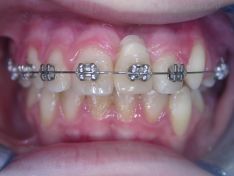

Nel caso qui visualizzato, invece, è stato realizzato un mantenitore per preservare lo spazio dopo avulsione traumatica dell'incisivo.

Il piccolo paziente per questa mancanza e per la malocclusione che lo affligge si presenta alla nostra osservazione. Dopo una prima fase di allineamento e di recupero dello spazio fisiologico per un futuro riposizionamento del dente, viene applicato all'apparecchio ortodontico fisso un dente modellato in resina per il recupero e il mantenimento dello spazio. Il bordo incisale del dente in resina, inizialmente allineato con i contigui, adesso risulta leggermente più apicale per movimenti degli stessi.